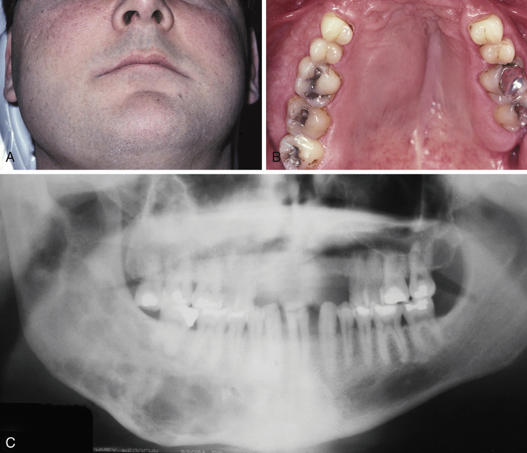

polyostotic fibrous dysplasia